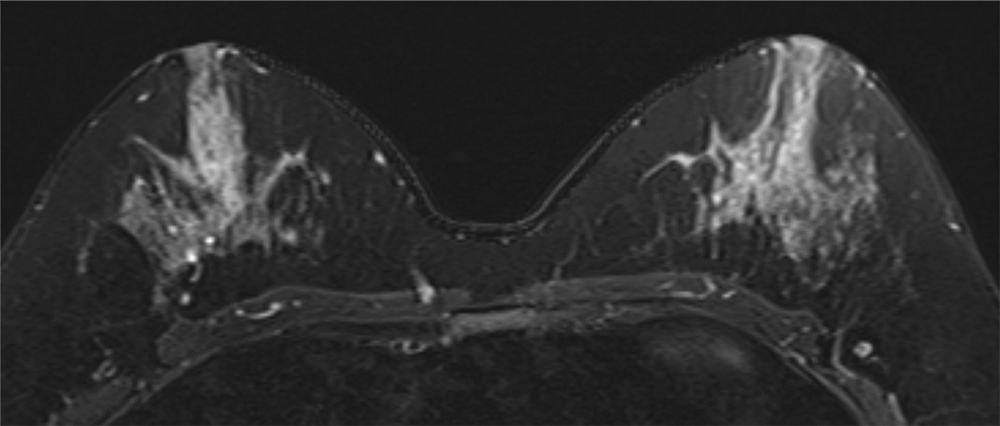

4. ダイナミックMRI 造影前 早期相 遅延相

左乳房内側にやや増強効果が目立つ領域があるがBPEも強いため同定が困難である。

ダイナミックMRI 早期相

ダイナミックMRI 遅延相